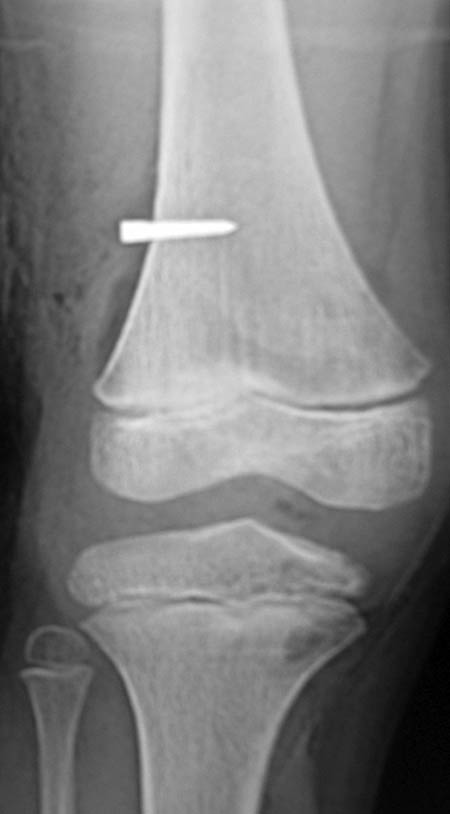

Los estudios por imágenes en casos de dolor en la cadera deben comenzar por las RX simples, pelvis frente, caderas panorámica frente, tomadas según el método de Siebenrock et al.13 (15° de rotación interna con la distancia entre la sínfisis pubiana y el coxis de 32mm en los hombres y 47mm en las mujeres), perfil quirúrgico bilateral y perfil de Louestein y el perfil de Lequesne (falso perfil) permite evaluar cobertura anterior en posición fisiológica. La correcta interpretación de estas imágenes y su correlación con el cuadro clínico, nos van a sugerir la necesidad de otros estudios que nos permitan aclarar el diagnóstico: la tomografía computada con reconstrucción tridimensional (TAC 3D), la RMN sin contraste. En la actualidad solicitamos siempre RX de pelvis frente, caderas panorámica, perfil quirúrgico, perfil de Dunn, (caderas en 90° de flexión y 20° de abducción), TAC 3D y en casos seleccionados la RMN con contraste (Figs. 4, 5, 6, 7a y 7b).14, 15, 16

Figura 4: RX Frente.

Figura 7b: Rx de un paciente de 48 años con cartílago aparentemente sano y calcificación del labrun.

En el momento de diagnosticar, se deben descartar todas aquellas lesiones degenerativas que provoquen trastornos morfológicos en la cara anterior del cuello femoral (Figs. 7b y 8b), sobre todo porque estas se presentan cuando la articulación ya tiene cambios, y esto incluye al cartílago hialino, en este caso se trataría de osteofitos, no de Leva, aunque el efecto pueda ser el mismo, su resección no detendrá el proceso degenerativo articular ya iniciado, aunque puede mejorar el cuadro clínico de manera transitoria.